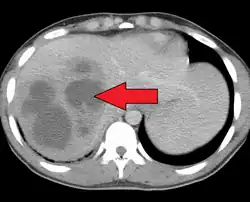

| A large pyogenic liver abscess presumed to be the result of appendicitis | |

A pyogenic liver abscess is a type of liver abscess caused by bacteria.